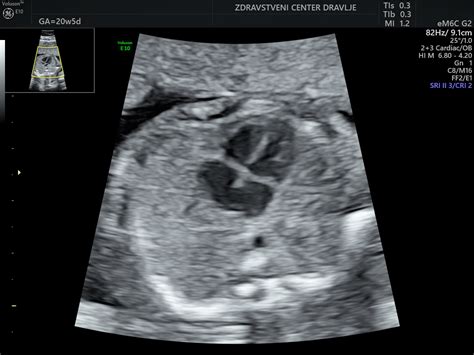

- Drugi ultrazvočni pregled: Okoli 20. tedna nosečnosti, znan kot morfološki pregled, kjer se natančno preveri razvoj ploda, rast, količino plodovnice ter strukturo in lego posteljice.